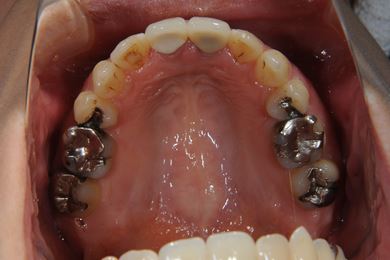

全顎矯正治療+セラミック治療

| 主訴 | 出っ歯 上顎前歯の並び | ||||||||||||||||||||||||||||||||

| 治療方針 | 上下歯牙がだいぶ前にでていて口が閉じづらい状態でした。なるべく金属が入っている歯を抜歯したいので、上下左右第二小臼歯を抜歯して、その隙間を利用して、口元をさげていきました。また、口元を最善の状態にうるために、抜歯スペースを使用したあと、上下左右のインプラントアンカー(釘)でより一層口元を後ろにさげていきました。ただの抜歯ケースよりだいぶ口元が下がっているのが分かります。抜歯したスペースががたつき(叢生量)で使用してしまう場合には、このような方法でより口元をさげることができます。お顔立ちがとてもよくなりました。とても協力していただけたので、しっかりと良くなることができました。 | ||||||||||||||||||||||||||||||||

| 治療内容 | 唇側矯正(ホワイト・上下左右第二小臼歯抜歯・上下インプラントアンカー)、オールセラミッククラウン1本(オールセラミック用土台1本)、ジルコニアフレームオールセラミッククラウン1本 | ||||||||||||||||||||||||||||||||